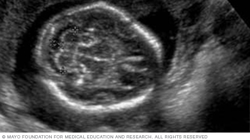

The image below shows a fetus's profile at 11 weeks of pregnancy, which is nine weeks after conception. At this stage, the head makes up about half of a fetus's length.